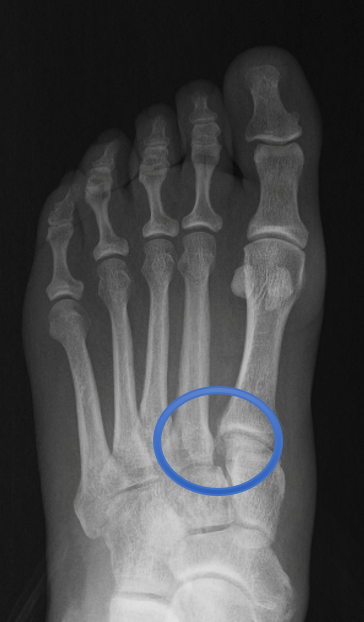

La articulación de Lisfranc se encuentra en el medio del pie, entre los huesos largos (metatarsianos) y los huesos del tarso medio (cuneiformes y cuboides). Piensa en ella como un puente que mantiene tu arco del pie estable y permite que apoyes tu peso de forma correcta al caminar o correr.

- Radiografías: muestran desplazamientos de los huesos.